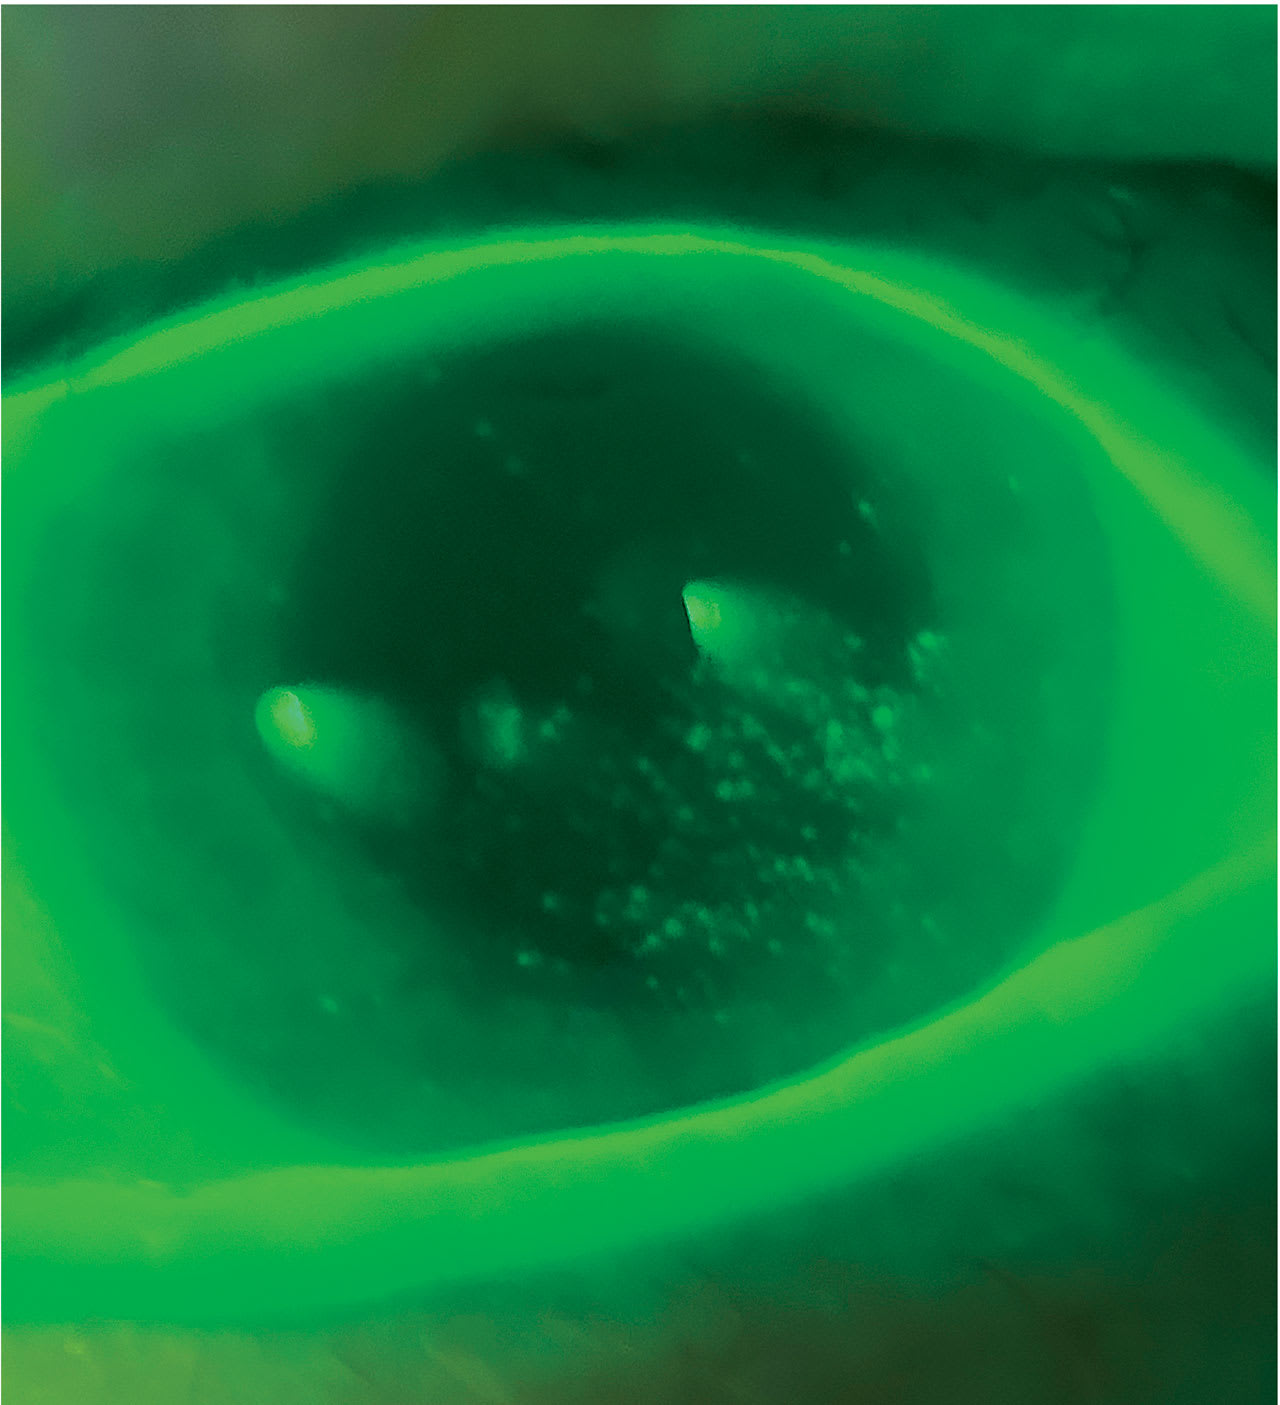

Contact lens solutions can cause toxicity or hypersensitivity reactions manifested as conjunctival redness, punctate staining, or corneal infiltrates in patients who have DED.12 Even at low concentrations, preservatives will cause some degree of cell damage to the ocular tissues.13 Therefore, recommending a contact lens holiday, daily disposable lenses, preservative-free lens care systems, and preservative-free rewetting drops can reduce this.